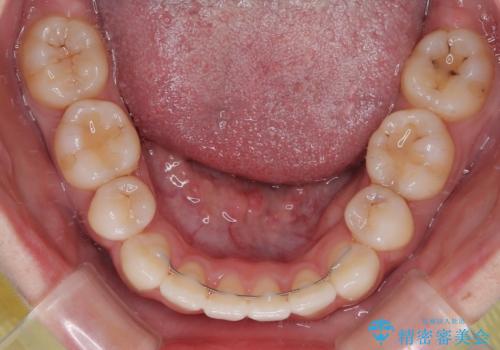

上下の保定用マウスピースの他に、デコボコの強かった下顎前歯にはワイヤーで保定をしています。